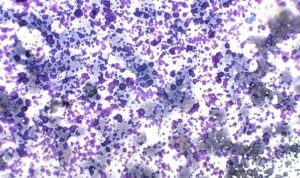

Figure 3. Excessive aspiration pressure causing widespread cell rupture (high‑grade lymphoma; Modified Wright’s, ×60).